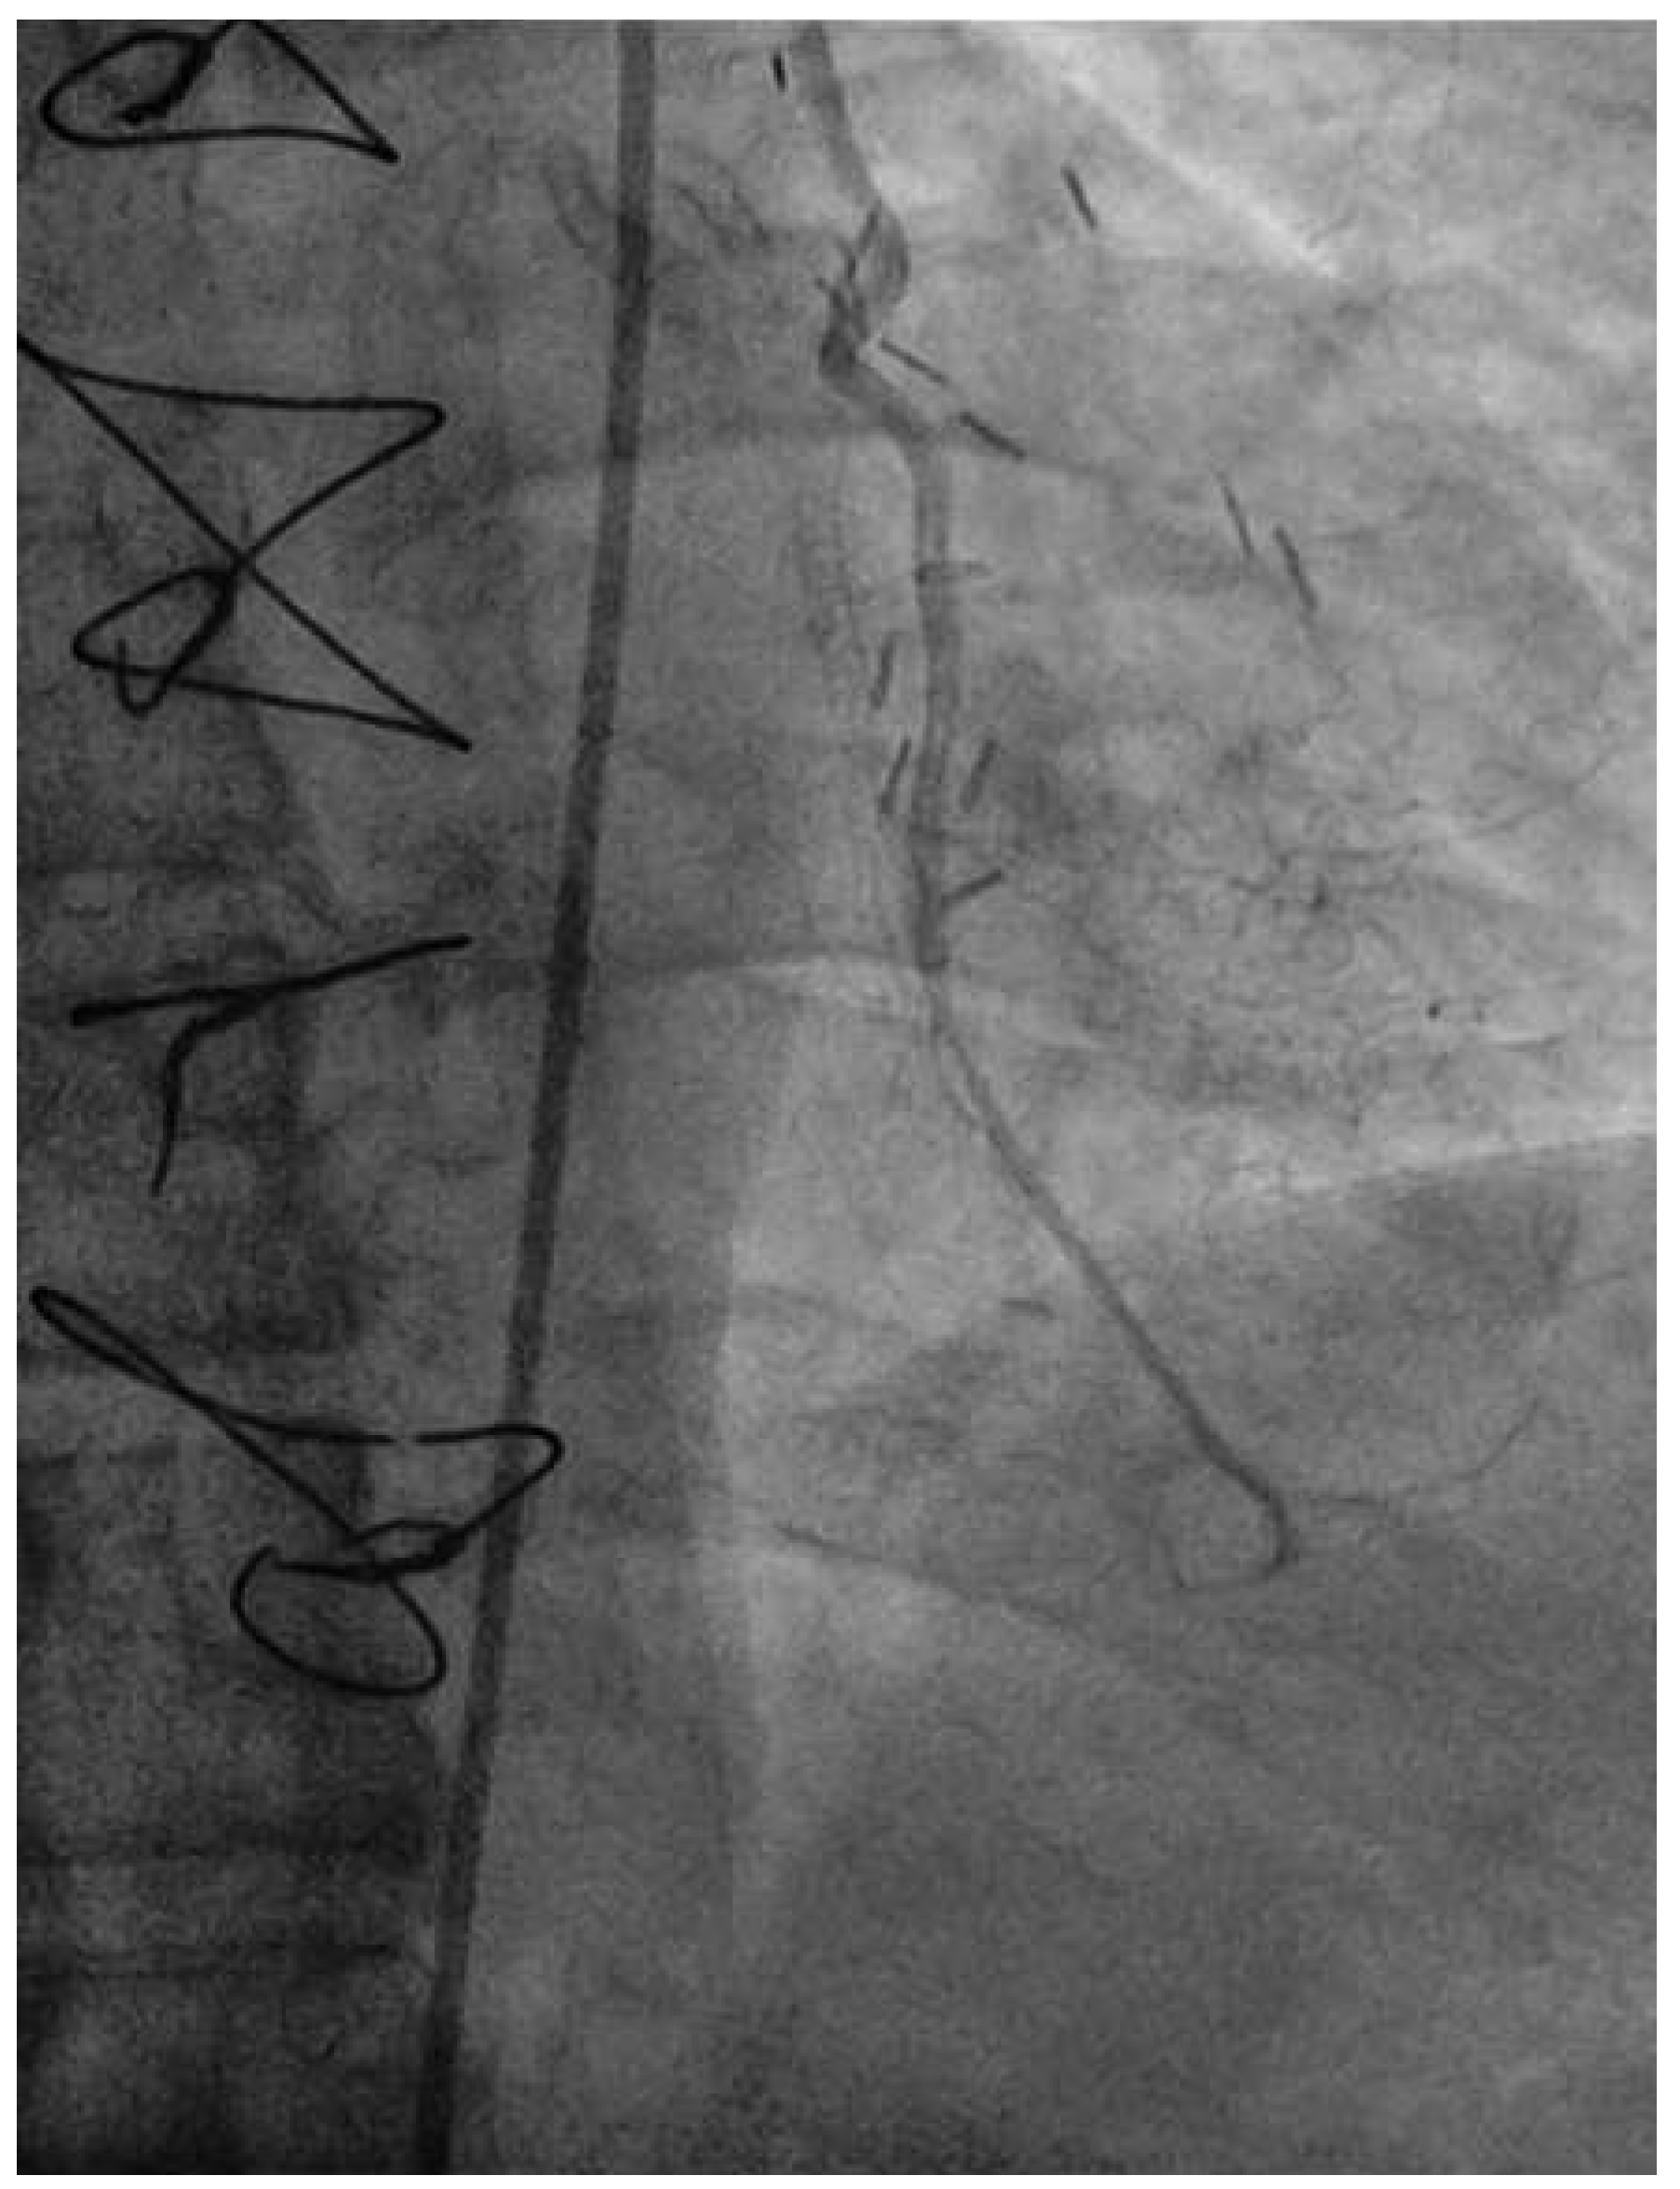

Coronary angiography of the left coronary system demonstrated severe left main stem (LMS) disease (Figure 1). The severe LAD in-stent restenosis was very eccentric and appeared to be restricting the origin of a sizeable diagonal branch, which also had severe disease. Distally, the LAD was occluded at the point where another stent had been inserted previously and just beyond a large septal perforator. The Cx had severe ostial disease and gave rise to a heavily diseased first obtuse marginal branch. The remainder of Cx and right coronary artery (RCA) systems were occluded proximally, with absent collaterals. The only patent graft was the LIMA, anastomosed very distally to the LAD (Figure 2). Following discussion, it was felt that neither Cx nor RCA were suitable targets for surgery and we therefore undertook intervention to the LMS and LAD / first diagonal bifurcation.

Figure 1. RAO 15°, cranial 40° view. of the left coronary system. Note the diseased LMS (A), the proximal LAD stent at the diagonal bifurcation (B) and the distal LAD stent (C).